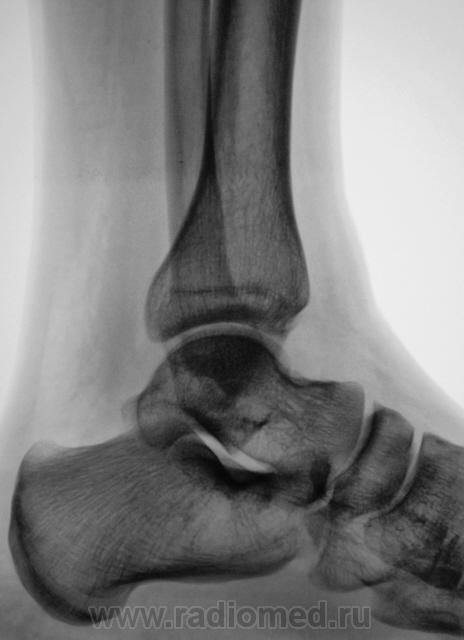

Травма. Пациент направлен на рентгенографию голеностопного сустава.

перелом обеих лодыжек и переднего отдела пяточной кости

Согласен кроме пяточной кости. Там - N.

Если, в пяточной кости "норма", то, что тогда, помеченное стрелками?